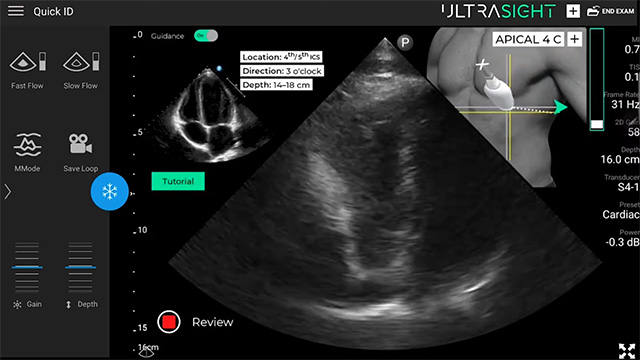

• AI 가이던스 솔루션이 촬영 위치, 방향, 깊이 등을 실시간으로 안내하는 장면.

화면 우측 상단에는 초음파 탐촉자(프로브)의 위치와 방향이 시각적으로 나타난다. /출처=울트라사이트 유튜브 영상 캡처

▲ AI 가이던스 솔루션이 촬영 위치, 방향, 깊이 등을 실시간으로 안내하는 장면. 화면 우측 상단에는 초음파 탐촉자(프로브)의 위치와 방향이 시각적으로 나타난다. /출처=울트라사이트 유튜브 영상 캡처